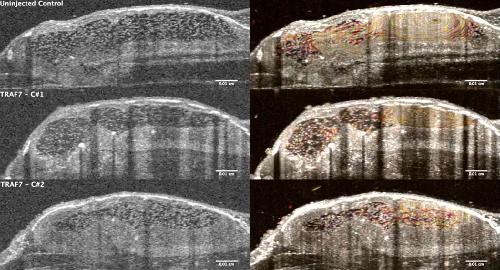

Pleiotropic role of TRAF7 in skull-base meningiomas and congenital heart disease., Mishra-Gorur K, Barak T, Kaulen LD, Henegariu O, Jin SC, Aguilera SM, Yalbir E, Goles G, Nishimura S, Miyagishima D, Djenoune L, Altinok S, Rai DK, Viviano S, Prendergast A, Zerillo C, Ozcan K, Baran B, Sencar L, Goc N, Yarman Y, Ercan-Sencicek AG, Bilguvar K, Lifton RP, Moliterno J, Louvi A, Yuan S, Deniz E, Brueckner M, Gunel M., Proc Natl Acad Sci U S A. April 18, 2023; 120 (16): e2214997120. |

Xenopus Tadpole Craniocardiac Imaging Using Optical Coherence Tomography., Deniz E, Mis EK, Lane M, Khokha MK., Cold Spring Harb Protoc. June 7, 2022; 2022 (5): Pdb.prot105676. |

Analysis of Craniocardiac Malformations in Xenopus using Optical Coherence Tomography., Deniz E, Jonas S, Hooper M, N Griffin J, Choma MA, Khokha MK., Sci Rep. February 14, 2017; 7 42506. |